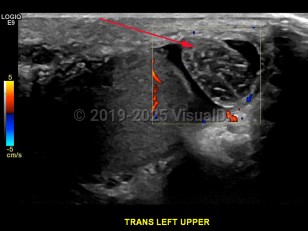

Testicular torsion is a medical emergency that results in a twisted spermatic cord and compromised blood flow to the testes with irreversible damage occurring in as little as 6 hours. A twisted spermatic cord initially results in lymphatic obstruction and then progresses to increased venous pressure, venous congestion, and ultimately decreased arterial flow leading to testicle ischemia and necrosis.

The main presenting symptoms are rapid onset of scrotal pain and swelling, often accompanied by nausea and vomiting. The patient may also complain of abdominal or pelvic pain, dysuria, fever, and an altered gait. Typically, testicular torsion occurs unilaterally, and patients may report previous episodes of similar scrotal pain that resolved spontaneously. Testicular torsion occurs most often in patients under the age of 20, although it can occur at any age with peaks occurring in neonates and during puberty. It is the leading cause of testicular loss.

Physical examination will show a raised testicle and absent cremasteric reflex. The testicle is often swollen and tender with an abnormal lie. Scrotal edema and tenderness may also be present, although the condition may be painless in approximately 10% of affected patients. The scrotum may also appear reddened or darkened on the affected side.